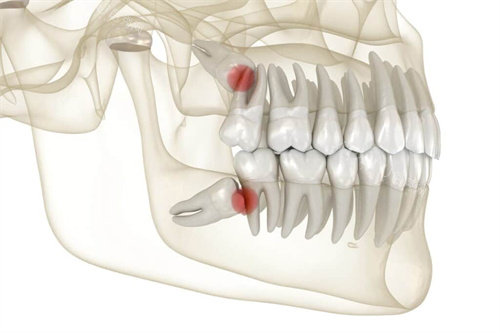

五、拔智齿价格